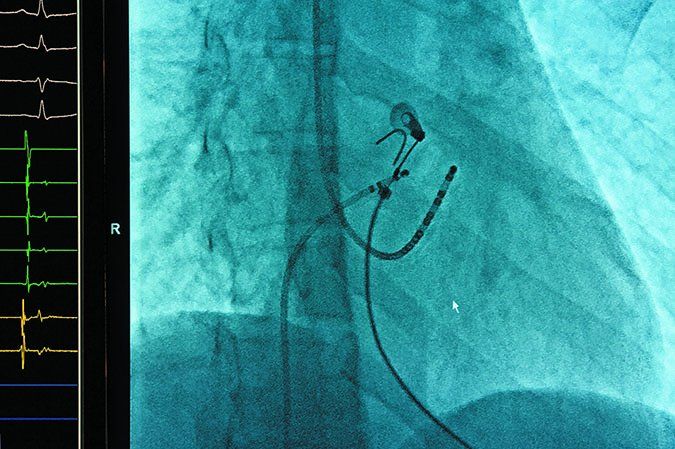

Atrial fibrillation (afib) is the most common arrhythmia in the world, yet many women know nothing about it. Afib is a disturbance in the hearts electrical system that causes the heart to beat irregularly. Although both men and women can be affected, women with afib tend to have worse symptoms, worse quality of life and a higher risk of stroke and death than men.